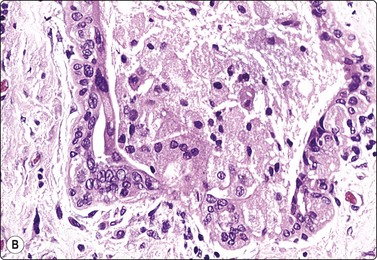

image image

Fig. 7.14 Cystic carcinoma

(A) Obviously malignant epithelial cells with a background of debris in aspirated fluid (MGG, HP); (B) Tissue section showing malignant cells lining the cyst wall (H&E, HP).